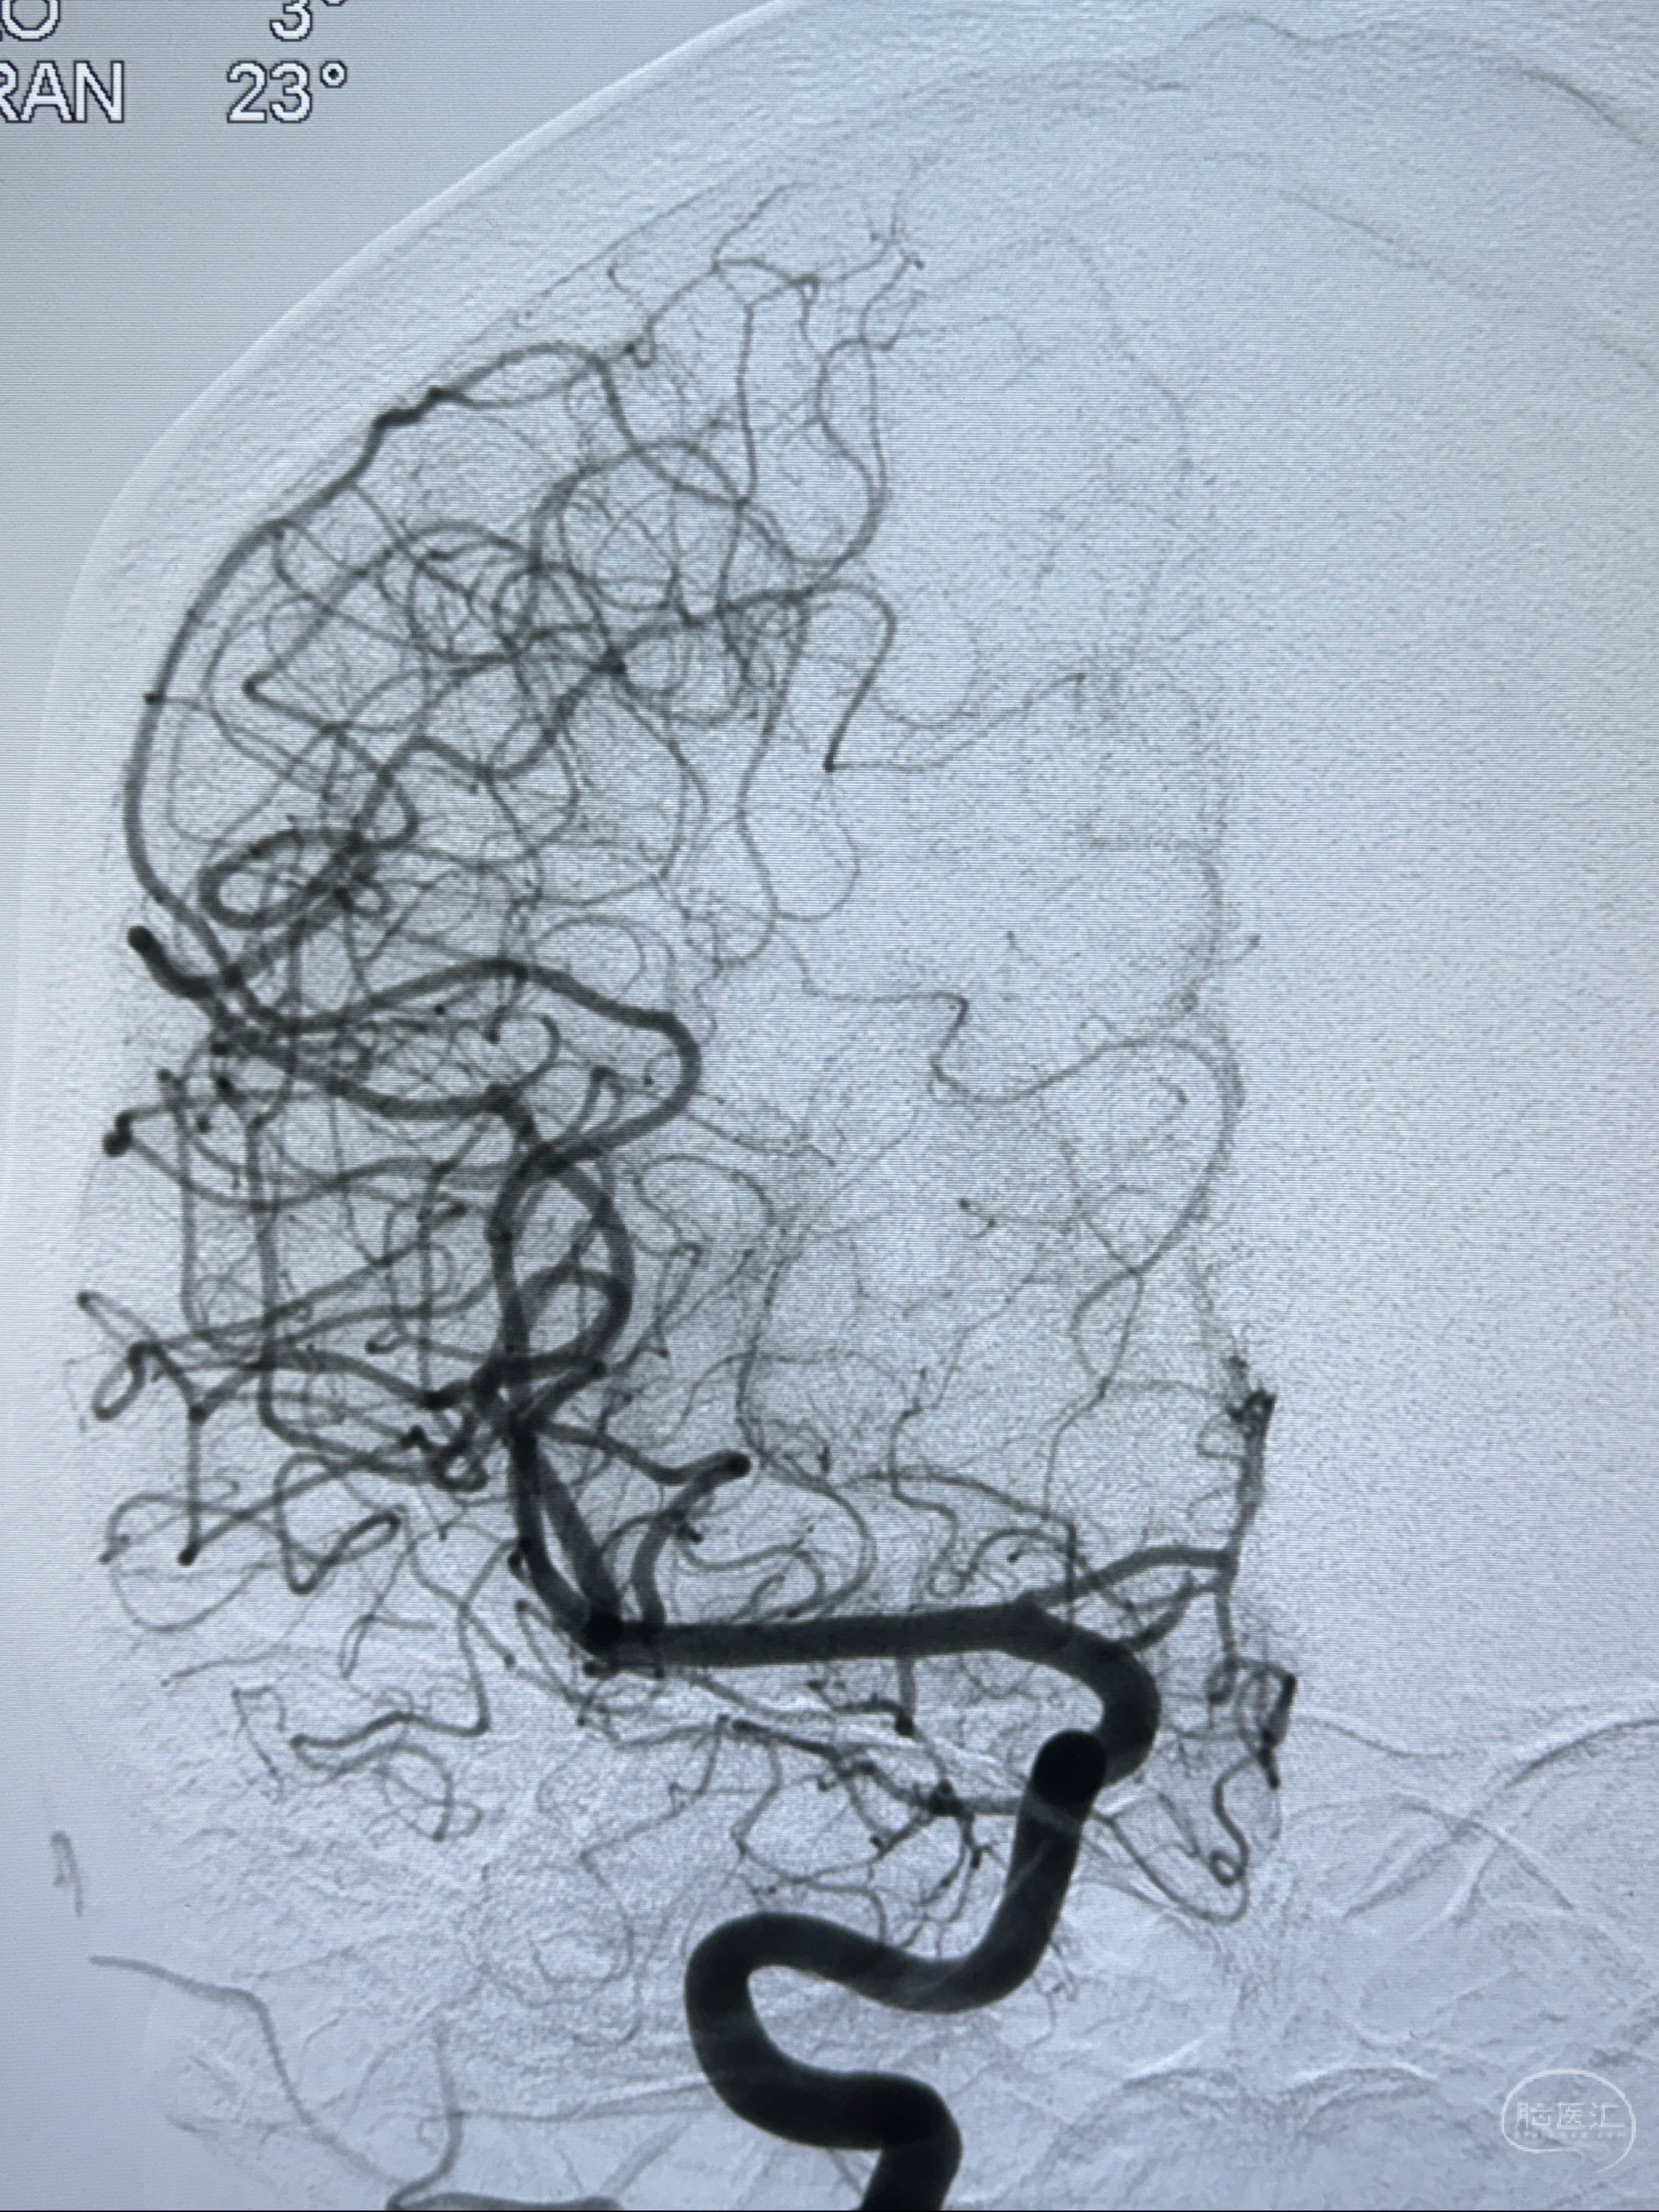

2023-11-13DSA:左侧颈内动脉眼动脉后壁动脉瘤

2023-11-29全麻下行NeuroformEZ4.5-20mm支架辅助栓塞